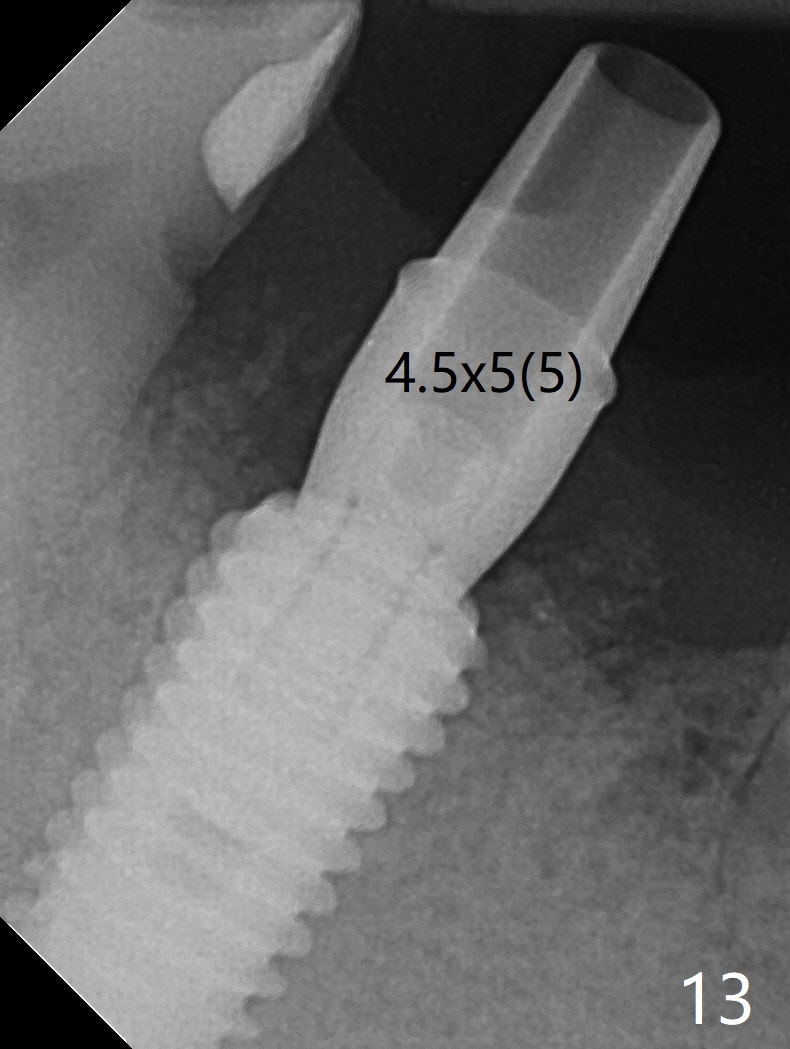

Although the tooth #30 has distobuccal root exposure (Fig.1 <), it is asymptomatic.  In contrast the tooth #31 with the distoocclusal caries (*) is symptomatic.  After use of 2 mm drill for 18 mm (lingual gingival margin), a calculated parallel pin is inserted (Fig.2 (D: 2 distal roots of the tooth #30)).  It appears that a 11.5 mm long implant is appropriate for the site; a 5 mm cuff is expected.  Following 4.8 mm drill, a 5.5x11.5 mm implant is placed initially (Fig.3) with an apical space (*) and clearance from the Inferior Alveolar Canal (red dashed line).  The implant is placed deeper with placement of a 6.5x4(5) mm abutment and bone graft (*, Fig.4,5).  After placement of collagen membrane over the graft, an immediate provisional is fabricated (Fig.6 P) with clearance from the opposing tooth (Fig.7 *).  There is no bone loss 3.5 months postop (Fig.8).  In fact the abutment has not been seated completely since its placement (Fig.4,5,8).  The crown/abutment dislodges 3 years 3 months post cementation (Fig.9).  The latter occurs for long incubation time because of opposing partial denture (Fig.10).  After trimming proximal surfaces (Fig.11: arrowheads), the abutment remains incompletely seated (Fig.11) due to possible crestal bone interference (Fig.11 *).  The smaller abutment by itself remains unseated (Fgi.12).  One size small one is completely seated (Fig.13).  Impression is taken.  Two weeks later the abutment margin is supragingival.  After screw torque at 20 Ncm, the crown is cemented with access hole.  Excess cement is removed.